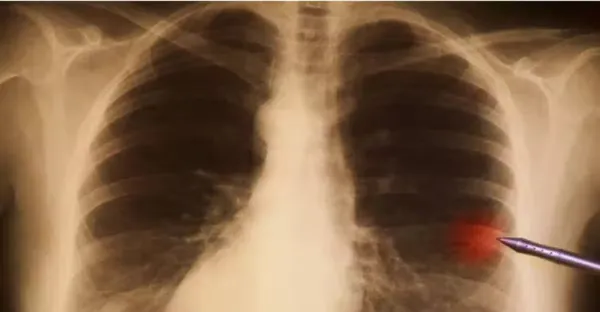

不抽菸不喝酒!45歲女確診「晚期肺癌」只因長期在做兩件事 5類高危人群要重視「早期癥狀」

全球一年1929萬人患癌!四大惡性腫瘤「一發現即晚期」 再次提醒:這4種食物「再愛吃也要忌口 」